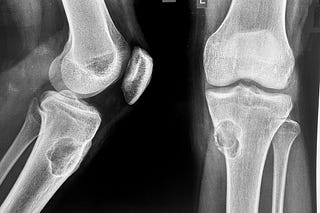

Case of the Day - 094 - 2025 09 01 - Between a Rock and a Hard Place

13-yrs old with a proximal tibial, bone forming, aggressive lesion, likely osteosarcoma with one failed biopsy.